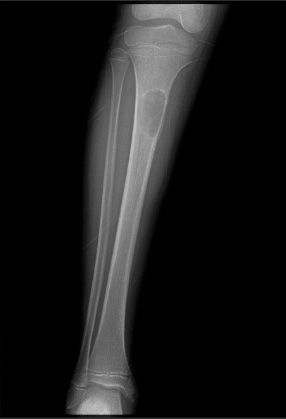

Osteofibröz displazi Campanacci hastalığı; nadir bir hastalıktır, tibia (kaval kemiği) ve fibulayı tutar. Özellikle tibianın 1/3 orta kısmında görülür. Tibia öne ve yana doğru eğilir. Kırık gelişmediği sürece ağrı olmaz. Patolojik kırk konservatif olarak tedavi edilir. Deformiteyidüzeltmek ya da deformite gelişmesini önlemek amacı ile cerrahi olarak tedavi edilir.